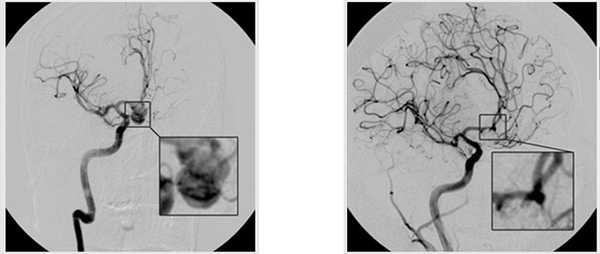

Хирургическая тактика временного клипирования применяется при операциях по поводу церебральной аневризмы (ЦА) в 23—52% случаев [1]. Известно, что впервые временное клипирование артерии артериального круга большого мозга выполнил G. Jefferson [1] в 1928 г. во время операции по поводу Ц.А. Превентивное временное клипирование, по некоторым данным, позволяет снизить частоту интраоперационных разрывов аневризм в 2,5—7 раз, т. е. до 4,2—15% [1]. Летальность после операций с использованием превентивного временного клипирования в 3—5 раз ниже, чем после операций с вынужденным временным клипированием, выполненным на фоне кровотечения из аневризмы [1, 2]. В настоящее время для выполнения временного клипирования применяют съемные клипсы с низким давлением браншей, не приводящим к повреждению интимы артерий [3]. Некоторые хирурги [4], учитывая эффективность и относительную безопасность превентивного временного клипирования, рассматривают возможность его рутинного применения в хирургии аневризм. К осложнениям временного клипирования относят ишемию головного мозга, ангиоспазм, повреждение эндотелия и тромбирование артерии, подвергнутой окклюзии [5]. Длительность временного клипирования артерий при открытых нейрохирургических операциях по поводу ЦА является одним из наиболее значимых факторов риска ишемии мозга [6].

Хирургическая тактика использования временного клипирования приводящего (-их) артериального (-ых) сосуда (-ов) коллегиально обсуждалась в каждом конкретном случае предстоящего нейрохирургического вмешательства на основании заключения нейрохирургического диагностического комплекса: МРТ, КТ головного мозга, КТ-ангиографии сосудов головного мозга, осмотра неврологом и нейрохирургами. Анестезиолог участвовал в обсуждении больных. Общая характеристика пациентов представлена в табл. 1. Таблица 1. Общая характеристика больных Примечание. ГБ — гипертоническая болезнь, ФП — фибрилляция предсердий; ЯБДК — язвенная болезнь двенадцатиперстной кишки.

Операция заключалась в проведении костнопластической трепанации черепа, широком раскрытии базальных цистерн с аспирацией ликвора, что позволяло уменьшить мозг в объеме и улучшить доступ к артериям основания мозга. Используя операционный микроскоп и микрохирургическую технику, выделяли вначале несущую артерию, затем по возможности одну или две отводящие артерии. В случае интраоперационного разрыва аневризмы это позволяло осуществить наложение временных клипс. Микрохирургическую операцию проводили с превентивным временным клипированием приводящего сосуда, на питающую аневризму артерию накладывали временную клипсу с короткими интервалами окклюзии сосуда. В некоторых случаях анатомические условия позволяли оперирующему нейрохирургу принять решение о клипировании шейки аневризмы без выполнения временной окклюзии питающего сосуда.

В условиях миоплегии и ТВВА пропофол +фентанил (глубина анестезии 32—38 по BIS-мониторингу) у всех пациентов отмечалось удовлетворительное интраоперационное состояние мозга. В обеих исследуемых группах по ходу операции оперирующие нейрохирурги, принимая во внимание анатомическую особенность аневризмы, ее шейки и приводящих артериальных сосудов, отказывались от тактики временной окклюзии приводящего сосуда и клипировали аневризму одномоментно. Таким образом, в основной группе и группе сравнения были выделены подгруппы пациентов, хирургическая тактика у которых состояла в клипировании ЦА без временной окклюзии приводящей артерии (табл. 3). Таблица 3. Сравнительная характеристика пациентов исследуемых групп с временным клипированием и без временного клипирования ЦА Примечание. *p

Сравнительная характеристика пациентов с временным клипированием ЦА в исследуемых группах представлена в табл. 4. Таблица 4. Сравнительная характеристика пациентов с временным клипированием ЦА в исследуемых группах

Максимальная продолжительность временного клипирования в основной группе с использованием цитофлавина составила 54 мин (суммарно за 4 эпизода) у пациентки 40 лет при клипировании аневризмы левая ПМА—ПСА локализации. Реакция пробуждения с последующей экстубацией отмечалась спустя 2,5 ч после операции без продленной седации в отделении реанимации; неврологического дефицита в послеоперационном периоде не отмечалось. Максимальная продолжительность временного клипирования в группе сравнения без использования цитофлавина составила 37 мин (суммарно за 4 эпизода) у пациентки 67 лет при клипировании аневризмы левая ПМА—ПСА локализации. В этом случае отмечалось замедленное пробуждение — через 8 ч после окончания операции с экстубацией через 9 ч от времени конца операции.